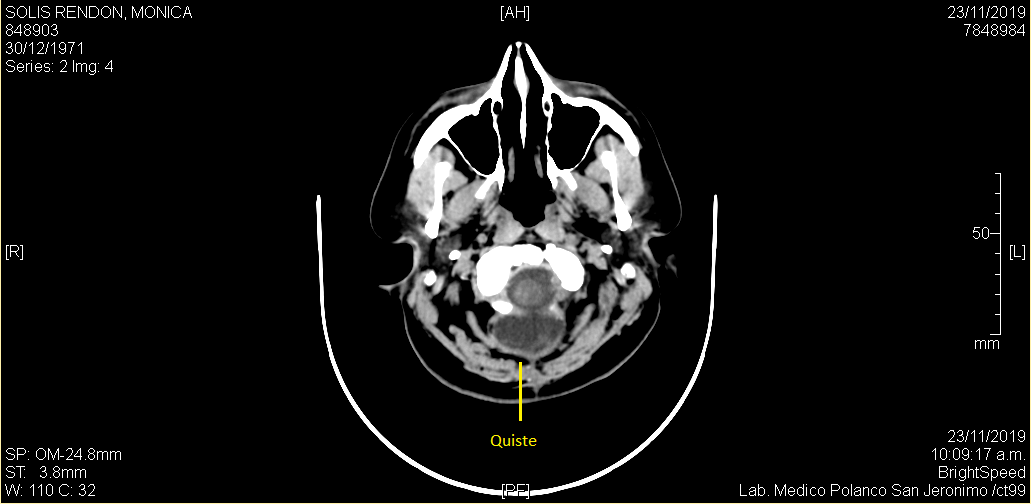

El 13 de diciembre tuve mi primer control fuera del hospital, previo a la cita, me saqué una tomografía y el ultrasonido. El doctor quería ver si el quiste redujo su tamaño, y así fue pero me pidió seguir con la medicina para el cerebro y el vendaje, del acné me dijo que iba a tardar algunos meses, lo mismo que la retención de líquidos, que no me preocupara por el peso ya que en unos meses, mi cuerpo eliminaría esos kilos de manera natural. Lo que no le gusto fue mi semblante, estaba demasiado pálida y amarilla así que me mando estudios.